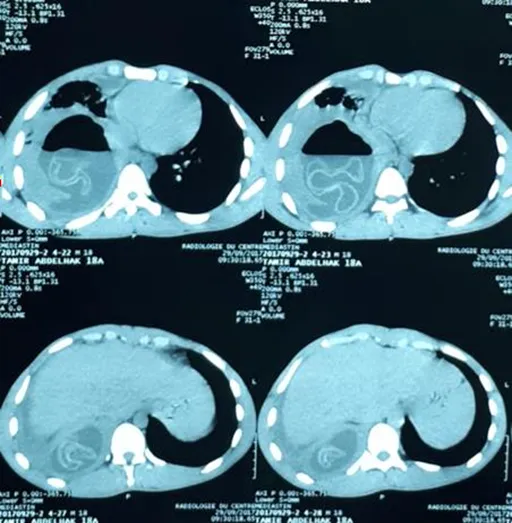

Observation 3Mrs. R.A, 61 years old, of rural origin, was operated 11 years ago for a hydatid liver cyst. She had presented for one year a purulent bronchial syndrome complicated by several episodes of medium-abundant hemoptysis, without hydatidoptysis or rejection of membranes, associated with right basithoracic pain and dyspnea. All of this in a context of conservation of the general condition. The chest X-ray had shown right basal opacity posing a problem of its seat (supradiaphragmatic, diaphragmatic or sub-diaphragmatic) (Fig-4). The chest CT scan showed a multivesicular cystic image resting on the diaphragm with endothoracic development (Fig-4).

Fig-4: a. Chest x-ray showing a right basal opacity posing a problem of its seat. b. Chest scanner showing a hydatid cyst resting on the diaphragm with endothoracic development